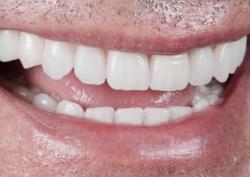

Анатолий, 61 год

Жалобы пациента:

Полное отсутствие зубов на верхней челюсти, сложности с приёмом пищи, дискомфорт при общении, стеснение улыбаться.

Что делали:

Результат:

Спустя две недели после процедуры Анатолий отметил полное восстановление жевательной способности. Новые зубы не вызывали ни малейшего раздражения или неприятных ощущений, позволили свободно наслаждаться любимыми блюдами.